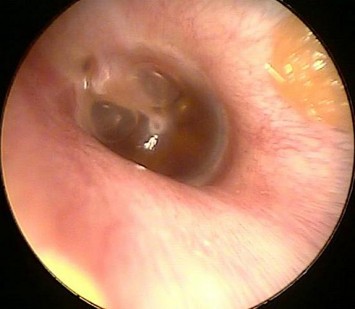

Вот как может выглядеть барабанная перепонка при экссудативном среднем отите.

Сначала врач проводит отоскопию у маленького пациента. Этот метод направлен на изучение состояния барабанной перепонки.

Её изменения могут варьироваться от незначительных до значительных:

- затемнение перепонки;

- выпуклость или вогнутость;

- приобретение перепонкой голубоватого оттенка;

- усиление;

- распространение до такой степени, что видна жидкость (в этом случае можно даже разглядеть, насколько плотный на данной стадии экссудат).